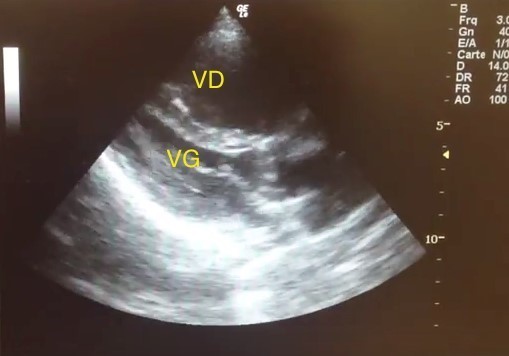

Voici les coupes de l’échographie cardiaque.

Coupe parasternale grand axe :

* VD = ventricule droit, VG = ventricule gauche.

Les autres données de l’examen sont : une fonction ventriculaire gauche conservée, un débit cardiaque abaissé, une pression dans l’oreillette droite élevée avec une augmentation des pressions artérielles pulmonaires systoliques.

Aspect de cœur pulmonaire aigu (CPA)

Pas d’épanchement péricardique sur les coupes d’échocardiographie transthoracique (ETT)

Images évocatrices de CPA.

Caractéristiques d’un CPA :

– augmentation de la pression artérielle pulmonaire systolique (PAPS), évaluée sur l’insuffisance tricuspide ;

– dilatation du ventricule droit (VD) [rapport VD/VG > 0,9] que l’on voit ici ;

– inversion de la courbure septale (bombement septal vers la gauche en proto-diastole) que l’on voit ici ;

– puis dysfonction VD.